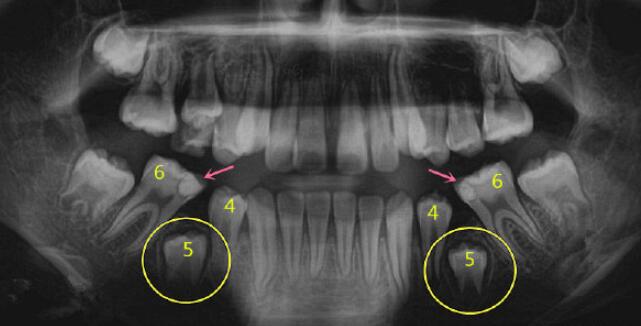

乳牙嚴(yan) 重齲壞不補牙,造成嚴(yan) 重的錯合畸形

5號乳牙由於(yu) 嚴(yan) 重齲壞拔除後,沒有做間隙保持器保持間隙,造成恒牙5由於(yu) 缺少乳牙引導以及沒有合適間隙,無法正常萌出。